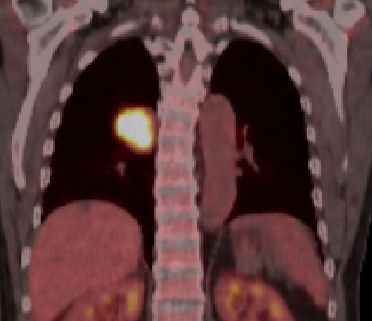

blauer Punkt 65mm großes Adenokarzinom des rechten Lungenoberlappens mit Infiltration der dorsalen Thoraxwand.